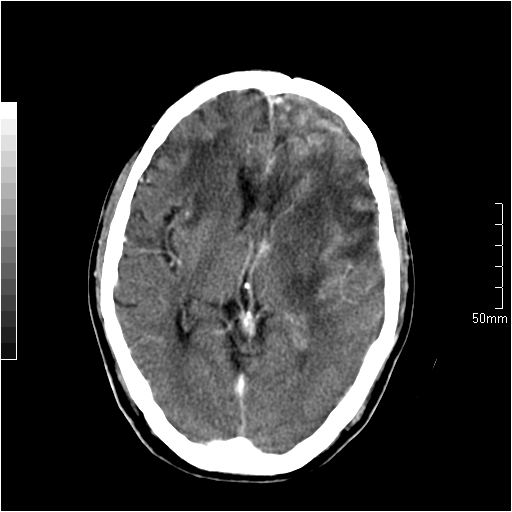

以下是引用天南地北在2007-6-25 12:39:00的发言:[br]有占位效应[br]支持术后复发

以下是引用zjzjr在2007-6-25 12:38:00的发言:[br]左侧复发,右侧转移。